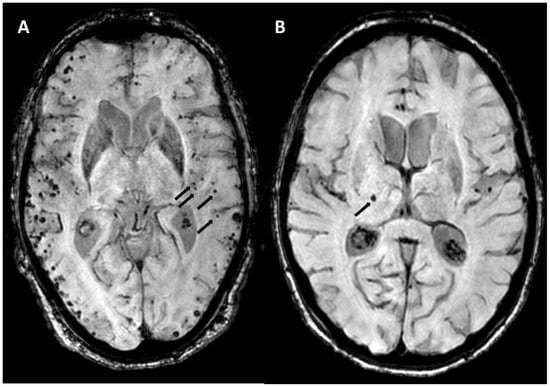

5.1.2. Multiple Cerebral Microbleeds

5.1.3. Convexity Subarachnoid Hemorrhage

5.1.4. Cortical Superficial Siderosis